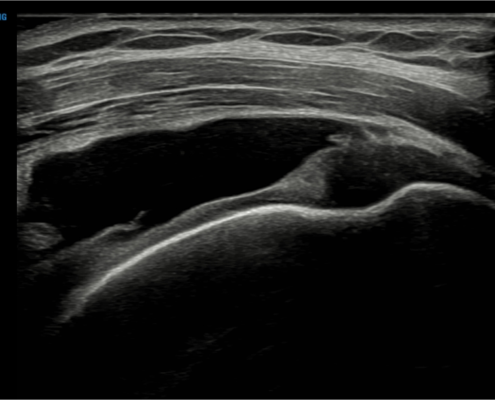

Met echografie kunnen we de schouderpezen goed beoordelen. Met behulp van een echo bepalen we de grootte en locatie van de scheur.

Echografie cuff ruptuur

We kijken naar verschillende soorten scheurtjes: